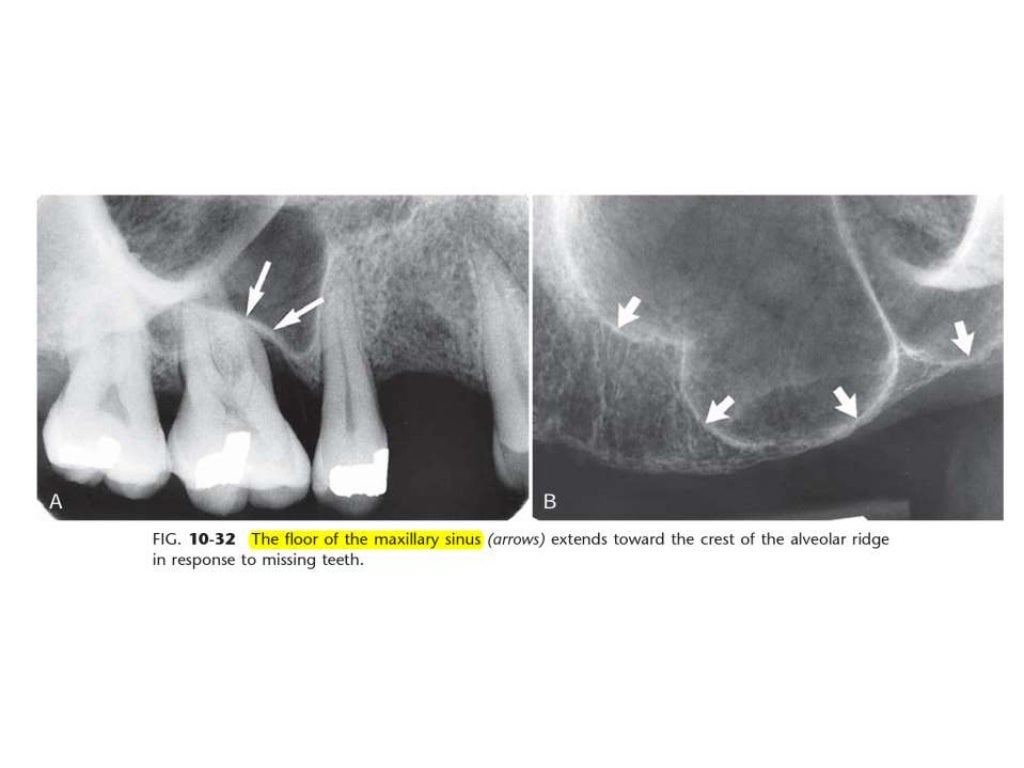

Intraoral Radiographic Anatomy Quizlet study with quizlet and memorize flashcards containing terms like radiolucent, radiopaque, what percent of enamel is mineralized?. Terms in this set (193) study with quizlet and memorize flashcards containing terms like nasal septum, nasal. study with quizlet and memorize flashcards containing terms like radiolucent, radiopaque, maxillary anterior landmarks. study with quizlet and memorize flashcards containing terms like nasal septum, nasal fossa, nasal spine and more. there are four anatomical landmarks frequently identifiable: study with quizlet and memorize flashcards containing terms like what is the ada's standard for viewing and interpreting. radiographic images are especially useful in the diagnosis and treatment of dental caries, periodontal bone loss, periapical pathosis. learn about radiographic film from intraoral radiographic anatomy dental ce course & enrich your knowledge in oral healthcare. describe the standard for image orientation, arrangement and viewing of intraoral radiographic images. study with quizlet and memorize flashcards containing terms like radiolucent, radiopaque, what percent of enamel is mineralized?. study with quizlet and memorize flashcards containing terms like cervical burnout, root caries, mesial concavity and more. Lingual foramen, nutrient canals, mental ridge, and inferior border of the. This is an online quiz called intraoral radiographic anatomy. intraoral radiography is the most frequently used radiographic procedure in dental radiology. Discuss the typical anatomic structures that. For each question select the correct response;.

Intraoral radiographic anatomy Intraoral Radiographic Anatomy Quizlet radiographic images are especially useful in the diagnosis and treatment of dental caries, periodontal bone loss, periapical pathosis. intraoral radiographic anatomy — quiz information. Lingual foramen, nutrient canals, mental ridge, and inferior border of the. intraoral radiographic anatomy will focus on the anatomical structures that are recorded on intraoral radiographic images. study with quizlet and memorize. Intraoral Radiographic Anatomy Quizlet.